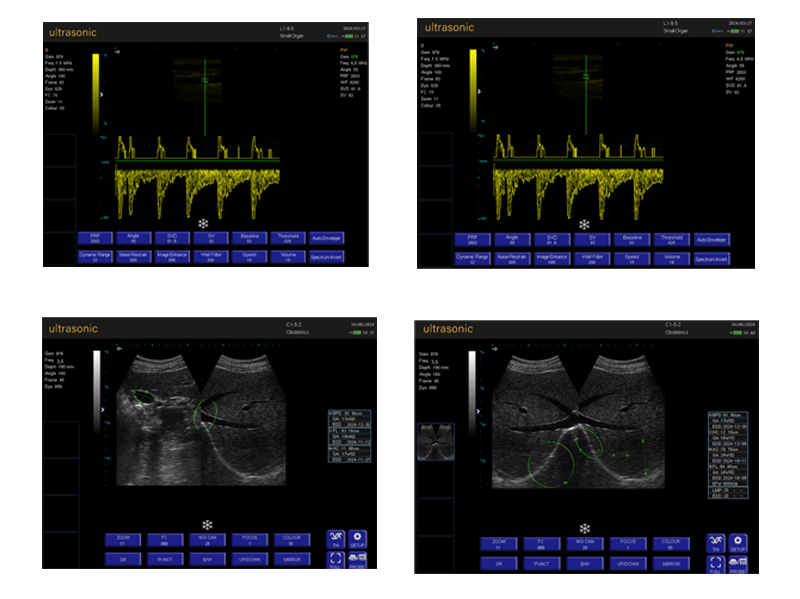

Laptop Color Doppler RK-7C

- Comprehensive obstetric measurement

The RK-7C is a notebook-style color Doppler ultrasound diagnostic instrument based on an ARM architecture system. It features a 15-inch high-definition LED screen (1024×768 resolution), providing clear images and easy operation. The device incorporates preset conditions optimized based on extensive clinical experience and a one-click optimization function, allowing for quick parameter adjustments for different departments and examination sites, thus improving work efficiency.

• Imaging Mode: B, B+B, B+M, M, 4B, PW

Product Gallery

c) Heart: 18 measurements including left atrium, right atrium, left ventricle, right ventricle, aorta, descending aorta, and aortic isthmus etc

d) Obstetric: 43 measurements including gestational sac, double parietal diameter, head circumference, abdominal circumference, femur length, fibula length,

head buttock diameter, yolk sac, abdomen, large and small brain, last menstruation, amniotic fluid, gestational age, expected date of delivery, fetal weight etc,

With different ethnic measurement formulas

e) Gynecological: uterine body, cervix, endometrial thickness, ovary, follicle